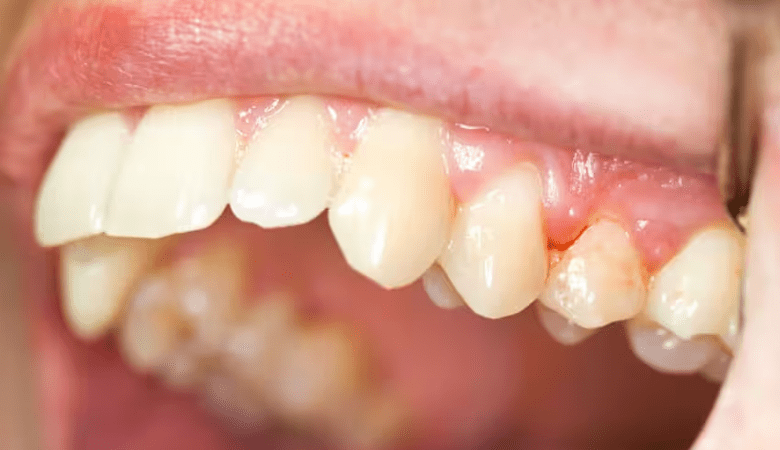

Tụt nướu là một trong những dấu hiệu viêm nướu răng (Nguồn: Internet)

- Nướu mềm và tụt khỏi chân răng: Nướu trở nên nhạy cảm, mềm yếu và có xu hướng tụt dần, để lộ chân răng.

- Thay đổi màu sắc nướu: Nướu chuyển sang màu đỏ hoặc hồng đậm hơn so với trạng thái khỏe mạnh.